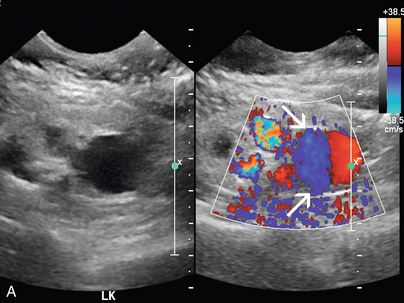

Синдром Щелкунчика

Феномен «щелкунчика» возникает в результате сдавления левой почечной вены между верхней брыжеечной артерией и аортой и может привести к гипертензии левой почечной вены, гематурии и образованию варикозно расширенных вен. Важно помнить, что у некоторых здоровых людей при КТ, МРТ или УЗИ можно обнаружить расширенную левую почечную вену. Следовательно, следует применять другие критерии, в том числе высокий коэффициент доплеровской скорости ( рис. 9-23 ) и высокий коэффициент диаметра вен, как описано в недавней литературе. Из-за сложности потенциального хирургического вмешательства может потребоваться измерение градиента давления между НПВ и левой почечной веной в качестве подтверждения до того, как будет диагностирована клинически значимая компрессия почечной вены. Визуализация крови из устья мочеточника при ретроградной уретероскопии также может быть полезной. Цветная допплерография может обеспечить неинвазивное подтверждение компрессии почечных вен с соотношением пиковых скоростей более 5:1, когда обнаружены коллатеральные вены. На КТ может наблюдаться резкое изменение калибра вен, когда вена пересекает СМА, обычно с «клювовидным» видом.

РИСУНОК 9-23 Щелкунчик с почечной веной. У пациента с необъяснимой гематурией спектральная допплерография преаортальной левой почечной вены (А) демонстрирует нормальный низкоскоростной поток, 8 см/с. (B) Когда вена пересекает аорту и SMA (допплеровские ворота), наблюдается видимое сужение с повышенной пиковой систолической скоростью, 103 см/с.